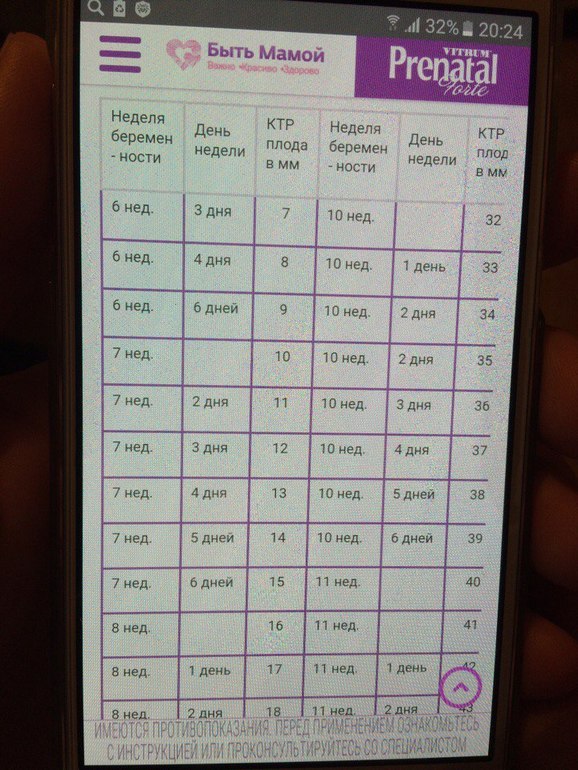

Спасибо большое, то есть если по ПЯ 7 неделек, тогда сердечко медленно немного( а по КТР не вернее судить о сроке? Я уже совсем запуталась(

Ну мне почему то больше кажется что у тебя 6 неделек и сколько то дней . Если так то у тебя нет отставания

Вот смотри табличку (фото 2 скинула) если по ней то у тебя да же 6 неделек нет. Нуууу мать возможно у тебя 5-6 недель ну или что то около 6 недель как то наверно так

Сасибо большое! Ну, по мнению узистки, которая была на дежурстве, у меня около 5,5 неделек. Не знаю, врачи очень довольны, что за 10 дней появился из "ниоткуда" эмбриончик с существенным достаточно КТР. В общем, решила выдохнуть и дождаться пятницы.